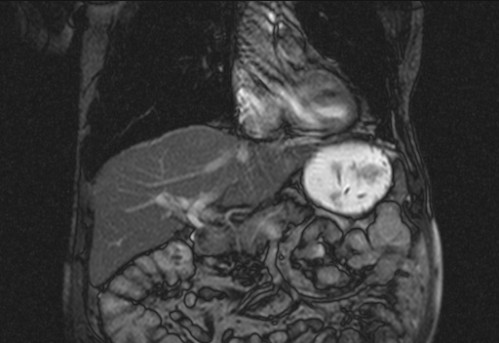

Auffälliges Abdomen bei der Vorsorgeuntersuchung einer älteren Dame

ICD: C64

68 Jahre alte Frau. Sie geht zur Darmspiegelung im Rahmen ihrer Krebsvorsorgeuntersuchung. Der Internist bemerkt bei der ergänzenden sonografischen Untersuchung des Abdomens einen auffälligen Befund.